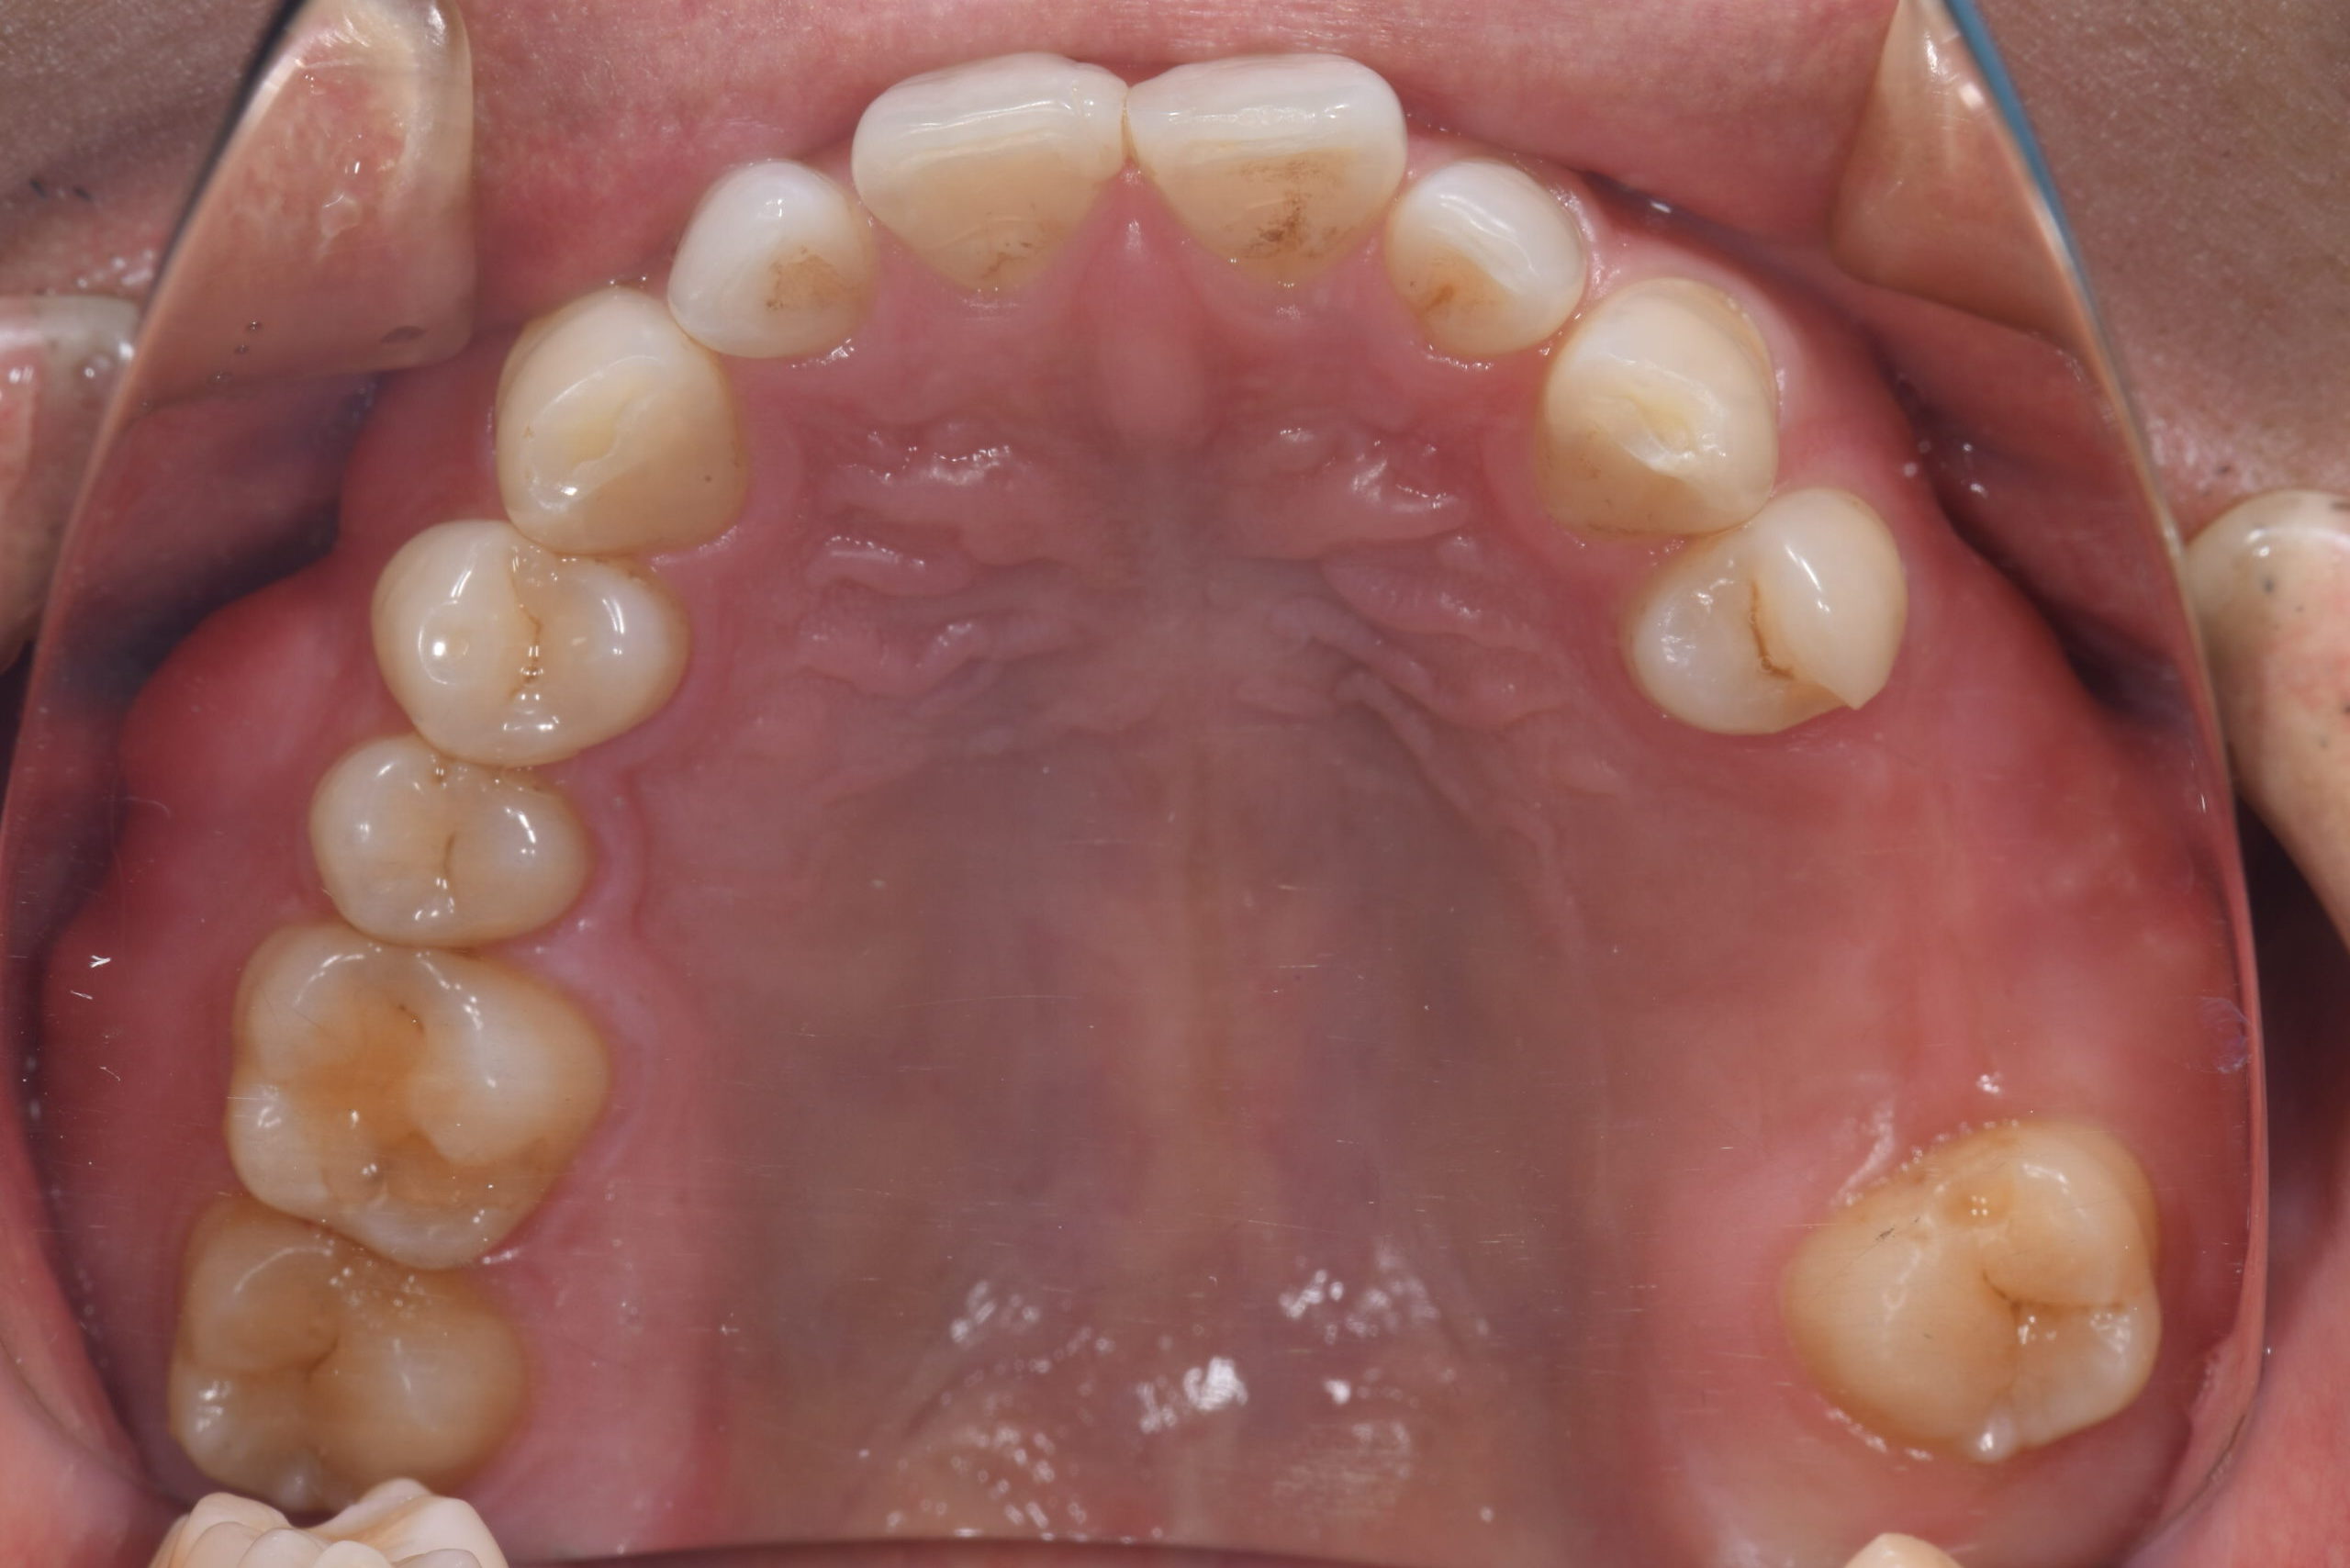

Before -上顎-

After -上顎-

| 施術内容 | 金属アレルギー予防を目的に、金属フリーの自費補綴へ変更。適合性・清掃性・審美性の向上が得られています。 |

|---|---|

| 治療期間 | 約4ヶ月 |

| 費用 | オールセラミックインレー 693,000円 |

| リスク・副作用 | 治療にともない、歯の破折や歯質の削合、場合によっては抜歯が必要となることがあります。また、金属や補綴物を除去する際に、完全に除去できない場合もあります。 |